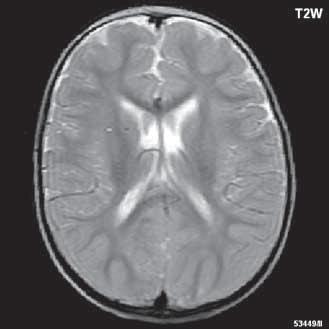

Obr. I.1.1h Fyziologický nález, již normální šíře subarachnoidálních prostor (věk 1,5 roku); stejný pacient jako na obr I 1 1f, g

Obr. I.1.1ch Fyziologický nález, již normální šíře subarachnoidálních prostor (věk 1,5 roku); stejný pacient jako na obr I 1 1f, g, h